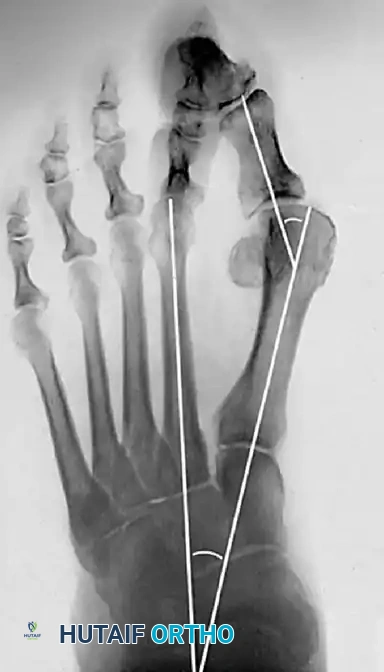

Image

Figure 2: Preoperative weight-bearing AP radiograph demonstrating a moderate hallux valgus deformity. The HVA is measured at 38° and the IMA at 17°. While pushing the upper limits of standard indications, modifications to the chevron technique can accommodate this pathology.